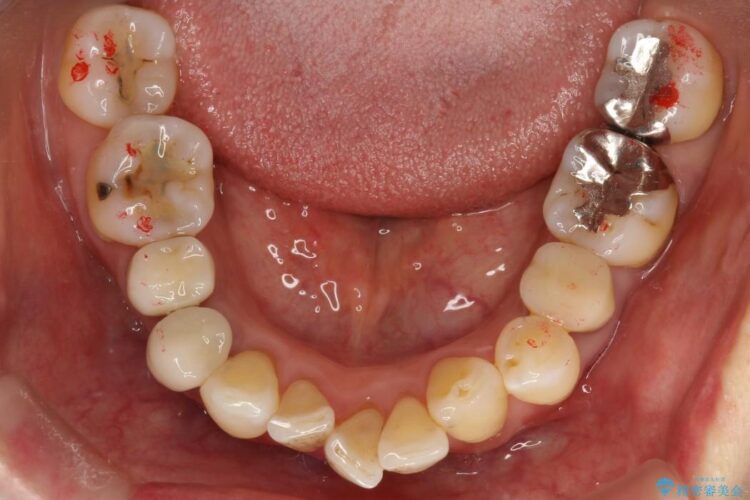

【50代女性】八重歯のインビザライン矯正 治療例

八重歯の改善を希望され来院されました。

当初はセラミックでの治療を希望されていましたが、噛み合わせと歯並びを治していく為に矯正治療を提案させていただき、インビザラインでの矯正を行う計画にしました。